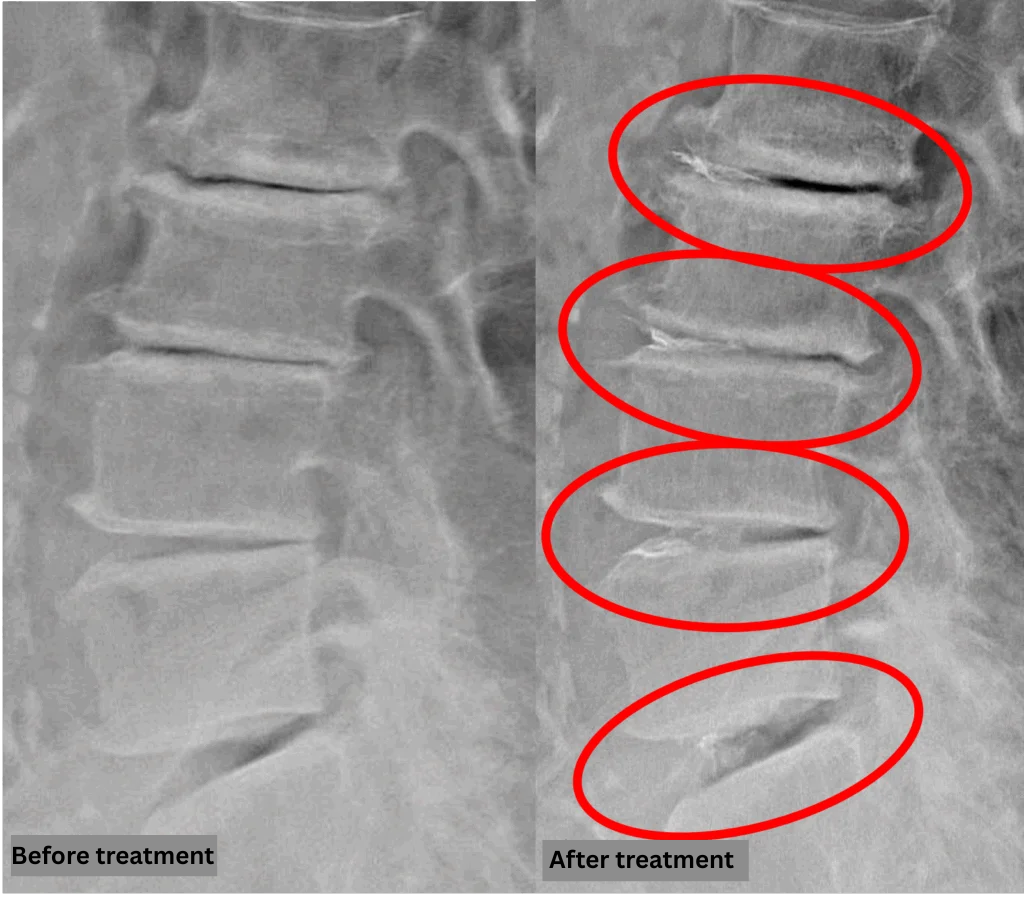

Imaging and findings

- L2/3, L3/4, L4/5: Disc degeneration and bulging.

- L5/S1: Disc degeneration, herniated disc, and spinal stenosis.

The above findings were also observed on the imaging.

Compression of the spinal canal caused by disc pathology at L2/3, L3/4, L4/5, and L5/S1 was considered the most likely cause of the patient’s symptoms.

After consulting with the patient, the Cellgel Method was performed on L2/3, 3/4, 4/5 and 5/s.